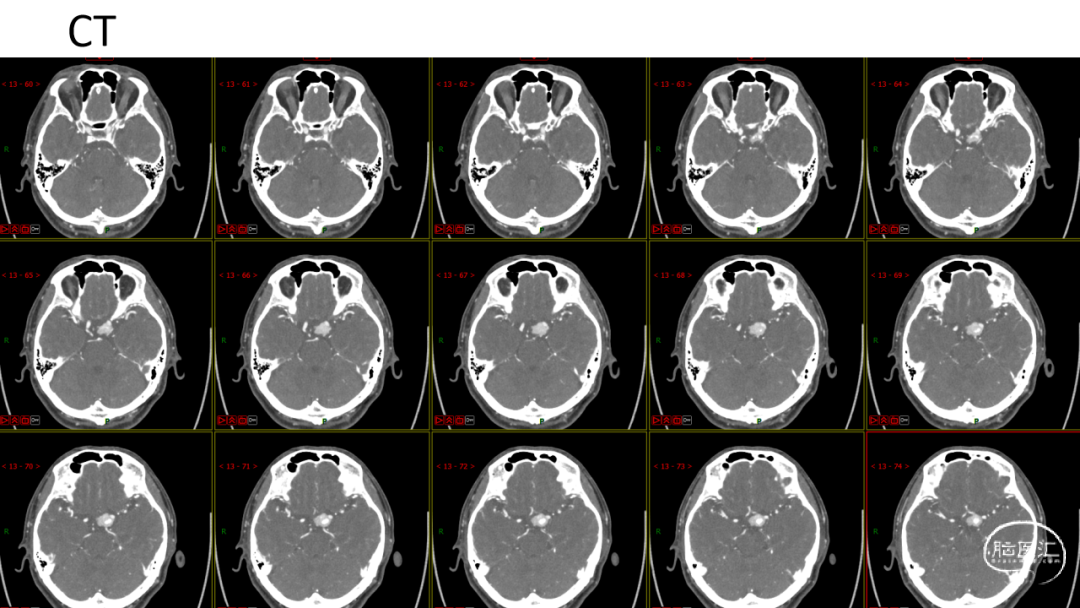

. 陶**,男,61岁

. 主诉:双侧视物模糊4年余,体检发现颅内肿瘤1月余

. 术前诊断:左侧鞍旁肿瘤 后床突脑膜瘤?

. 鉴别诊断:1.血管外皮细胞瘤;2.神经鞘瘤;3.软骨瘤或软骨肉瘤。

. 手术方案:翼点入路,硬膜外磨除前床突,充分分离侧裂,暴露颈内动脉及其分支,视神经、动眼神经并予以保护,由间隙进入先行处理肿瘤基底,后分块切除肿瘤。